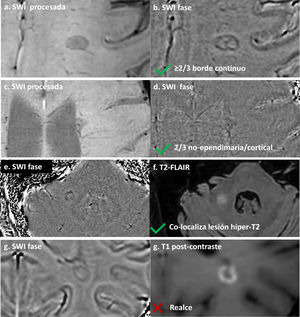

El consenso NAIMS de 2024 define una PRL como una lesión que demuestra un borde discreto con propiedades paramagnéticas sobre secuencias sensibles a la susceptibilidad, continua a lo largo de al menos dos tercios del borde externo de la porción de sustancia blanca de la lesión, co-localizada con un núcleo de lesión T2-hiperintenso y no captante, y visible en al menos dos cortes consecutivos o en dos planos ortogonales30. La definición completa, incluidos los criterios de exclusión, se proporciona en la tabla 2 e ilustrado en la figura 3.

Identificación de lesiones con borde paramagnético. (a, b) SWI procesada (a) e imagen de fase (b) que muestran una lesión con borde paramagnético continuo a lo largo de más de dos tercios del perímetro, cumpliendo criterios de PRL. (c, d) Lesión periventricular en SWI (c) y fase (d) con borde continuo a través de todo el borde de la sustancia blanca; el borde ependimario (flecha) queda excluido de la evaluación según el consenso NAIMS. (e, f) Imagen de fase (e) y T2-FLAIR (f) que demuestran la colocalización necesaria del borde paramagnético con un núcleo de lesión hiperintenso en T2. (g, h) Criterio de exclusión: imagen de fase (g) muestra un borde hipointenso en una lesión con realce anular en T1 post-gadolinio (h). Las lesiones captantes deben excluirse de la clasificación PRL.

Consideraciones prácticas. La identificación de PRL requiere experiencia técnica y protocolos optimizados. Dada la complejidad y dependencia de la intensidad de campo de 3T, las PRL deben interpretarse con precaución, especialmente en centros sin amplia experiencia; por ello, los criterios de 2024 asignan a las PRL un papel diagnóstico más limitado que el del CVS. La detección de PRL requiere secuencias de ecos de gradiente con reconstrucción de imagen de fase. Aunque las reconstrucciones tipo SWI son aceptables, se recomiendan mapas de fase para una visualización óptima del borde30. La detección es más fiable a 3T, aunque factible a 1,5T con protocolos optimizados32. Los principales riesgos interpretativos incluyen venas que corren junto a los bordes de la lesión, que pueden imitar un borde paramagnético. Las lesiones captantes deben excluirse, ya que el borde paramagnético refleja inflamación crónica—no aguda—. Se ha descrito una fiabilidad entre evaluadores del 90–97% en centros experimentados, aunque el acuerdo puede ser menor en entornos no expertos30.